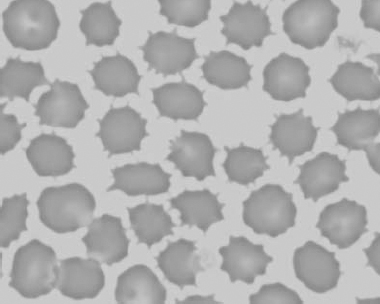

Figure 1.21 Bovine (calf) blood film showing marked poikilocytosis (normal?) (also see color section).

Figure 1.22 New methylene-blue-stained Canine blood film showing reticulocytes (also see color section).